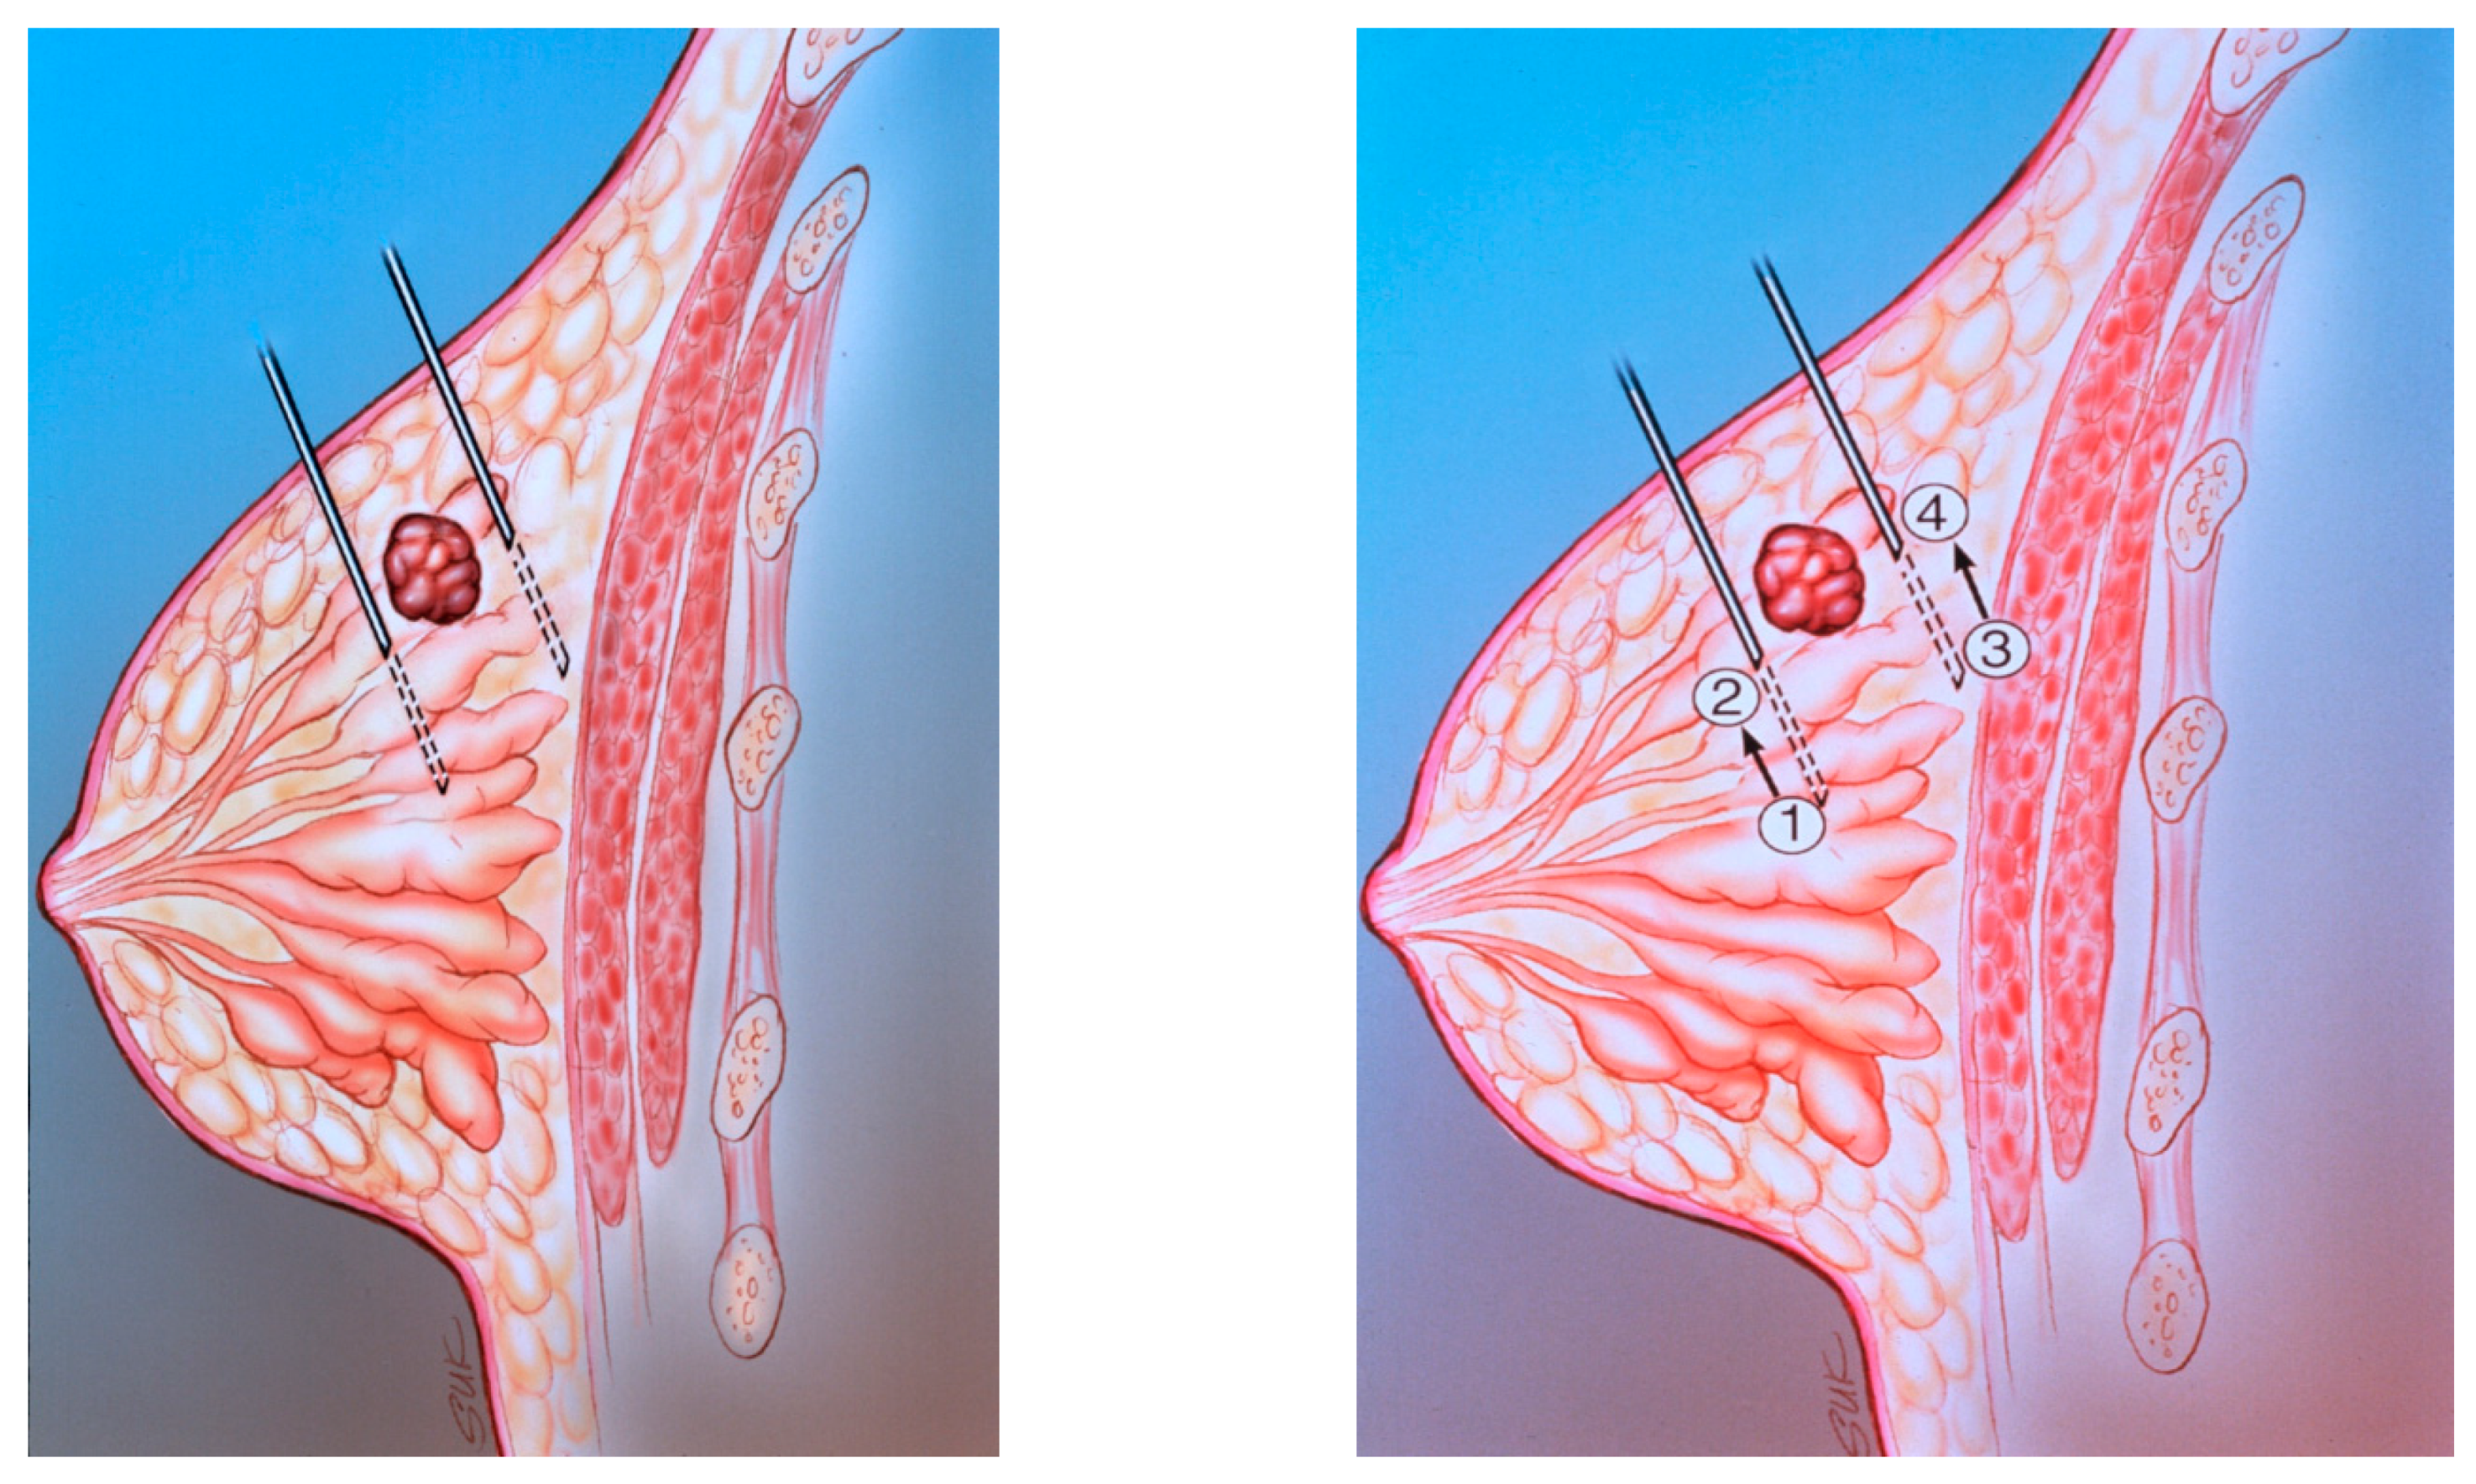

Figure 11. (A) The diagram shows peritumoral placement of two needles. (B) The localizing needles are placed with the tips at positions 1 and 3. The radiopharmaceutical is injected at positions 1 and 3. The needles are then withdrawn to positions 2 and 4. The radiopharmaceutical is then injected at positions 2 and 4.

Two tuberculin syringes are added to the standard procedure tray (Figure 4) for mammographically-guided SLNB. The radiopharmaceutical is kept in a lead container until the time of injection. Four mL of Tc-99m-sulfur colloid is injected in divided doses through the localizing needles (Figure 5). Hawkins, Homer, spinal (Figure 6) and Kopans needles have been used for mammographically–guided SLNB. After the injection of Tc-99m-sulfur colloid, saline is injected through tuberculin syringes to flush the localization needles (Figure 7).

6. Subareolar, Intradermal and Peritumoral Injections

Prior reports [26,27,28] have described a high degree of accuracy for intradermal injections of the isotope at the superolateral aspect of the tumor, probably secondary to communication between intraparenchymal and overlying dermal lymphatics. In a study comparing two different injection techniques (peritumoral and intradermal), lymphoscintigraphy was performed on 99 patients who underwent peritumoral and intradermal injections on separate days. Intradermal injections were performed either in the skin overlying the tumor or periareolar in the quadrant of the tumor. Ninety-four patients had positive peritumoral and/or intradermal accumulations. Fifty-two patients had complete concordance with axillary nodal uptake. In 30 patients, only peritumoral identification of the axillary nodes was successful and in nine patients, only intradermal identification of the axillary nodes was successful. Internal mammary nodes, visualized after peritumoral injection in nine patients, were not visualized by the intradermal technique. The authors concluded that intradermal injections are complementary to peritumoral injections (Figure 11) for patients with breast cancer [25].